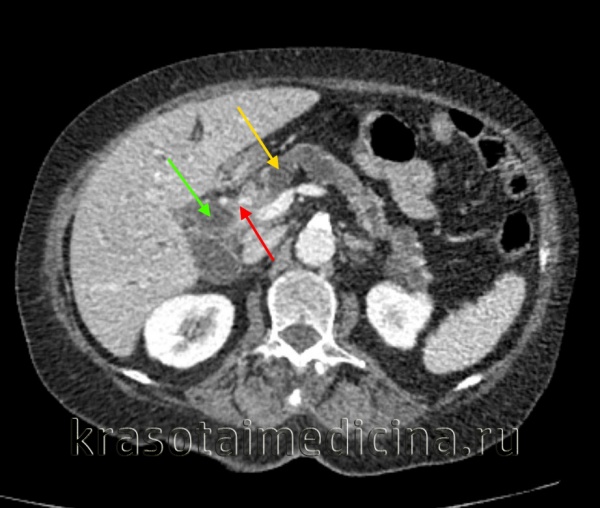

КТ ОБП. Внутрипротоковая холангиокарцинома (опухоль Клацкина) холедоха (красная стрелка). Расширенный холедох (зеленая стрелка). Расширенный главный панкреатический проток (желтая стрелка).

КТ ОБП (этот же пациент). Опухоль Клацкина холедоха (красная стрелка). Расширенный просвет холедоха до зоны обструкции (зеленая стрелка).